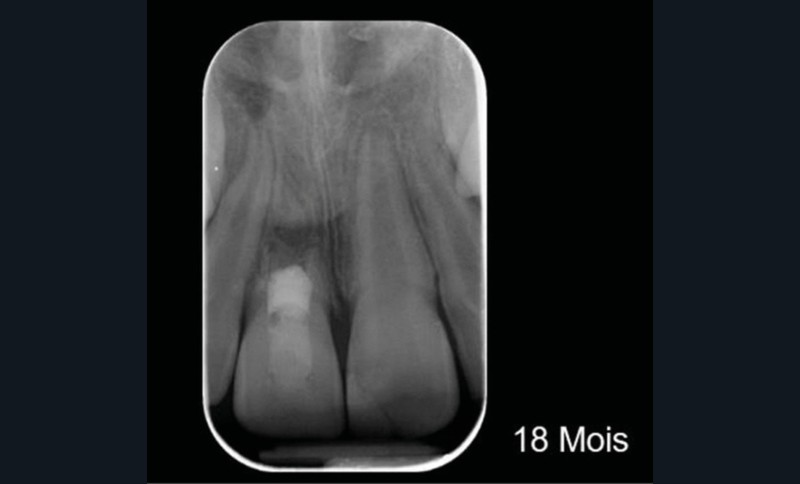

Ce cas clinique est particulier et illustre parfaitement l’évolution que suit l’endodontie depuis une dizaine d’années. Sans entrer dans le détail technique, cette dent expulsée avait été repositionnée dans son alvéole et un premier traitement de régénération intracanalaire tenté. Malheureusement suivi d’un échec. Le jeune âge de la patiente a été une motivation particulière pour tout tenter dans le but, au moins, de gagner du temps. Après plusieurs séances d’hydroxyde de calcium, l’apexification a été réalisée comme cela était possible. Le contrôle à 18 mois confirme que l’acharnement a payé.

Plus que sur l’éventuelle « prouesse technique » – qu’en tant que praticien nous pouvons être tentés de saluer –, il faut s’arrêter sur la facilité qu’a la biologie de stabiliser une situation pourtant désespérée, lorsque les conditions de remise en conditions saines sont mises en place.

Cet exemple clinique, et d’autres, nous conforte dans l’idée que le cognitif prend progressivement le pas sur la technique. Qui l’eut cru en endodontie ?